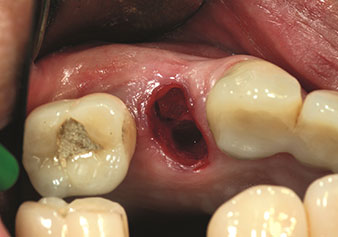

Situation following piezosurgical extraction

Fig. 2: Situation following piezosurgical extraction. Photo: © Dr Torsten Conrad (Bingen am Rhein)

W&H also offers the perfect solution for the internal sinus lift.

Following preparation of the maxillary sinuses with the corresponding instrument set (Fig. 3), the new Z35P instrument (Fig. 4) is used to lift the membrane hydrodynamically. The same instrument set can also be used for piezosurgical preparation of the implant bed in increasing diameters (Figures 3 and 4 included with the kind permission of Dr Mario Kirste, Frankfurt/Oder).

Preparation of maxillary sinus floor and lifting of Schneiderian membrane (Z35P instrument)

Fig. 4: Preparation of maxillary sinus floor and lifting of Schneiderian membrane (Z35P instrument). Photo: © Dr Mario Kirste (Frankfurt / Oder)